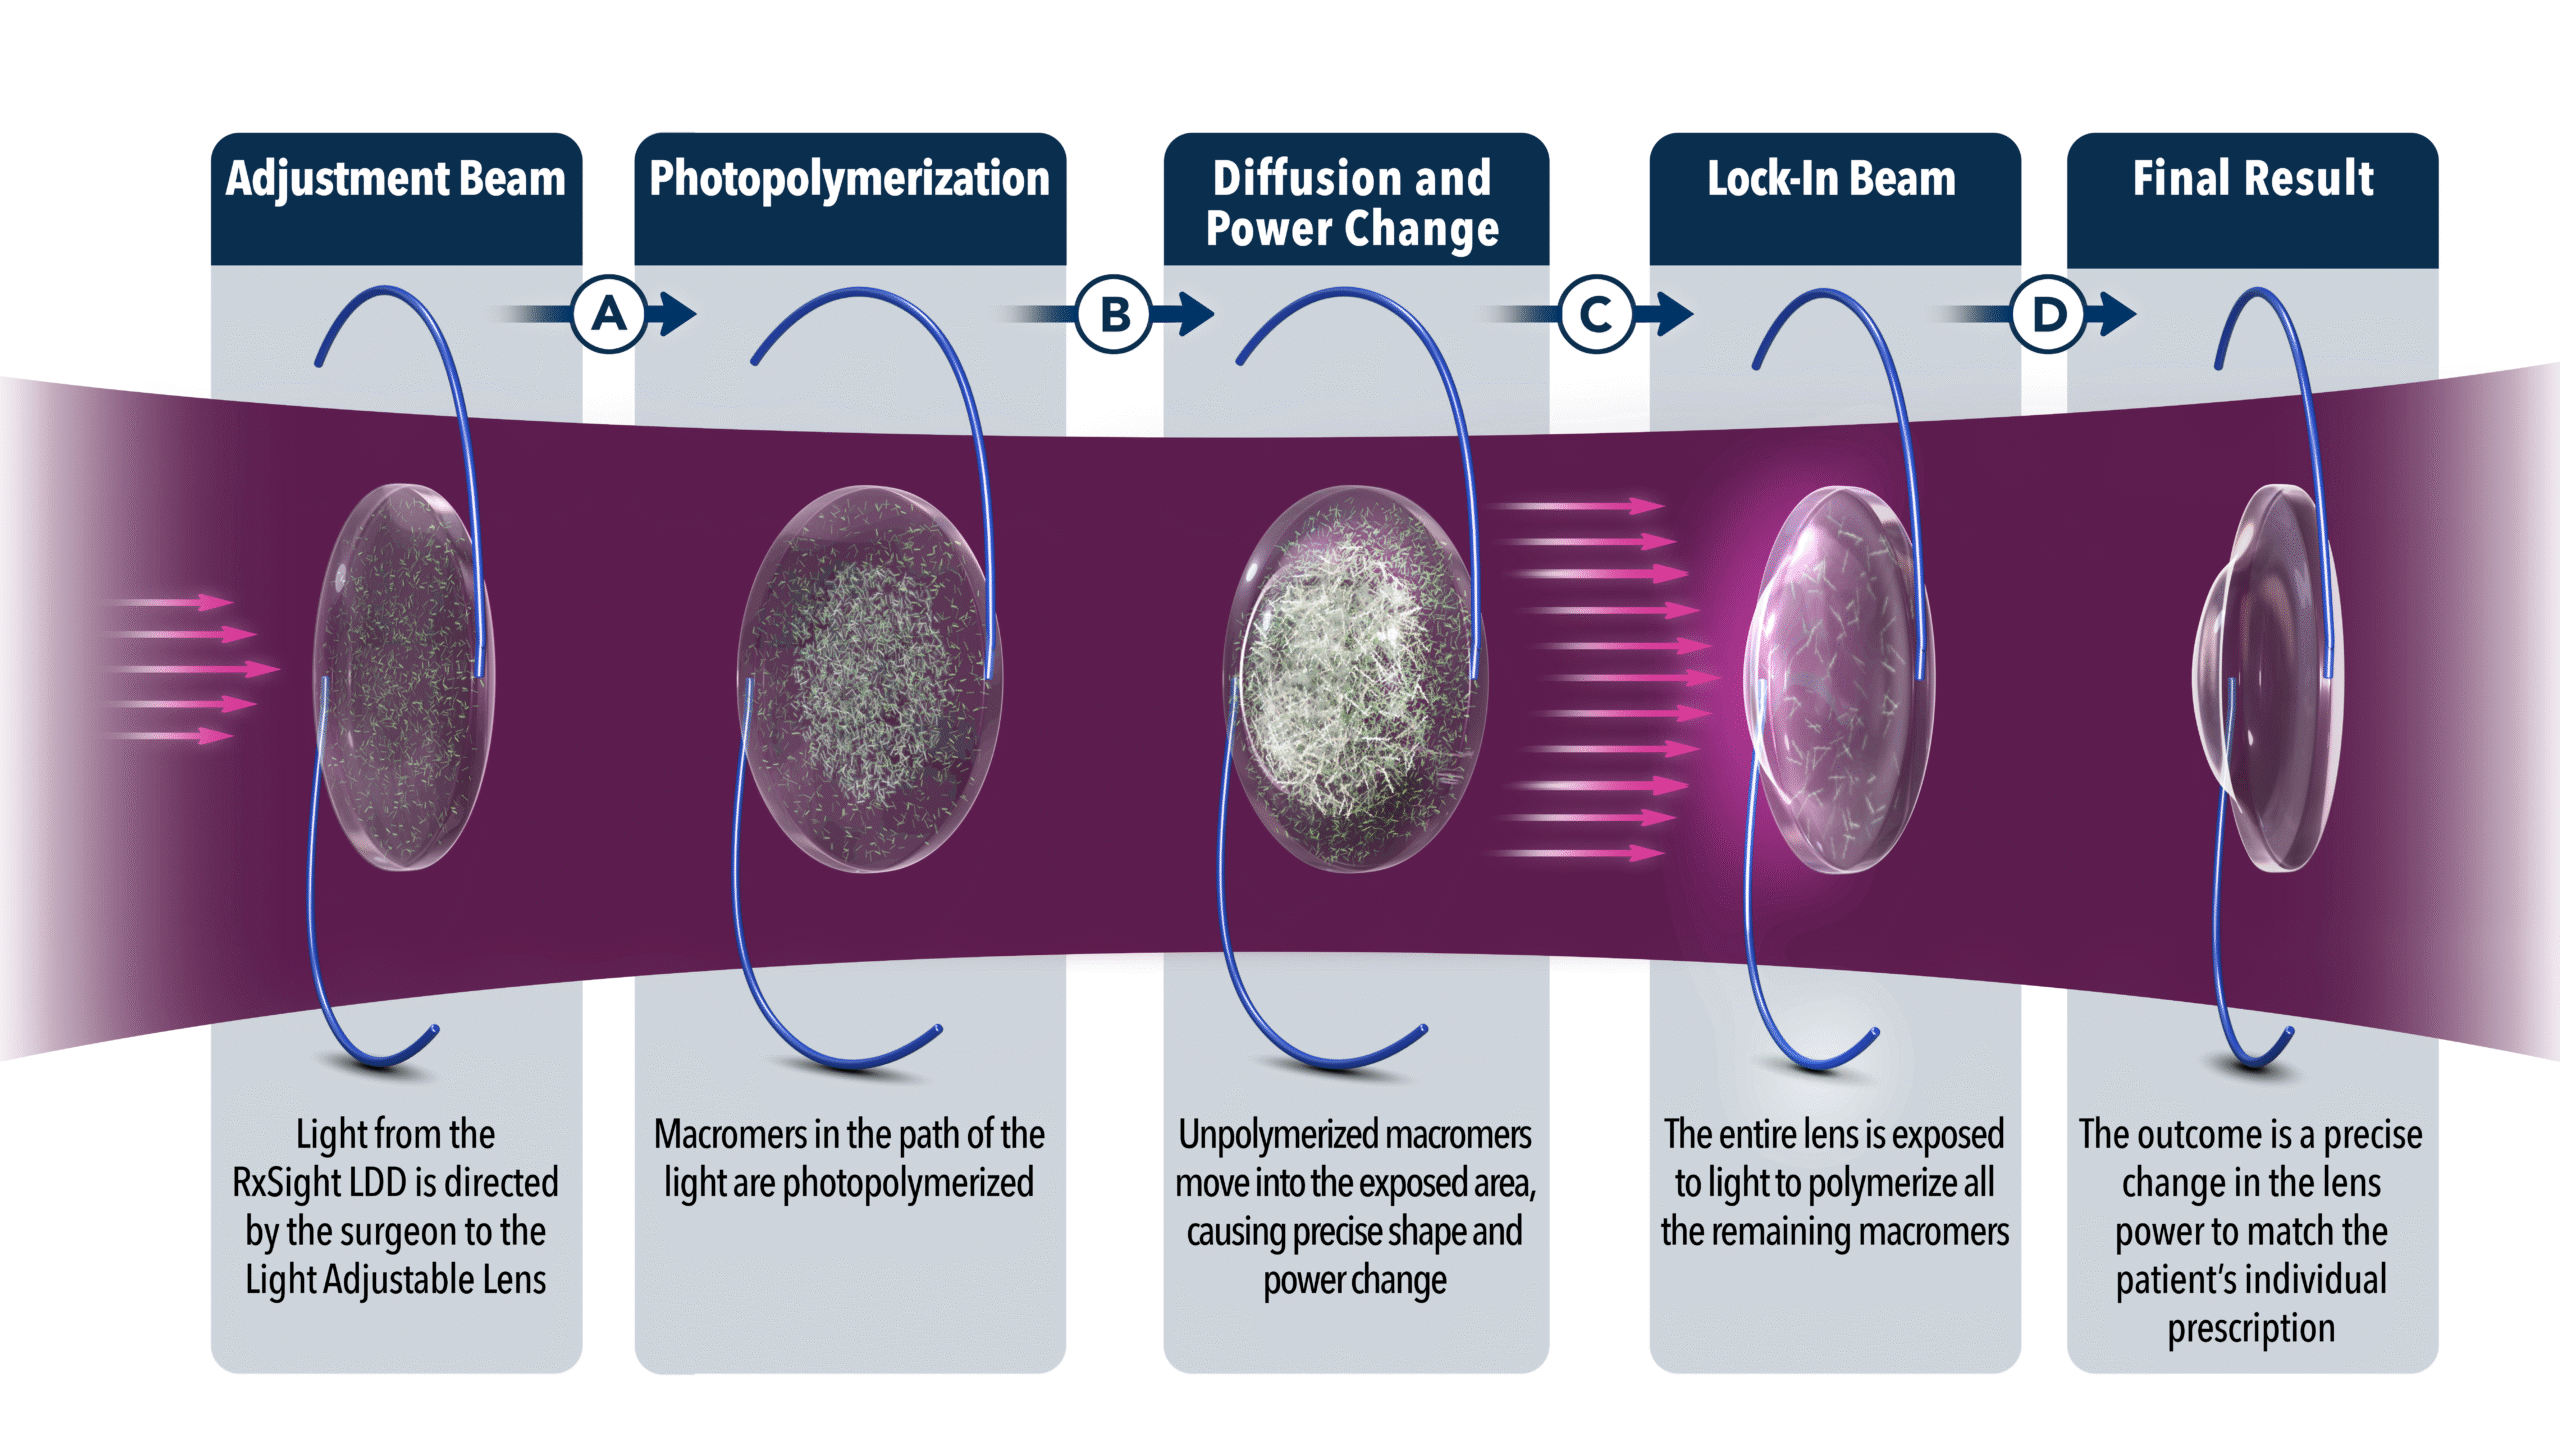

What is a Light Adjustable Lens?

The Light Adjustable Lens (LAL) is an intraocular lens placed at the time of cataract surgery that allows the surgeon to adjust the power AFTER cataract surgery is finished. Prior to this IOL’s approval, we extensively measured the patient’s eyes with multiple computers, lasers, and imaging devices to customize the IOL for each patient. We also have ORA to help make decisions during surgery and to fine tune astigmatism correction after the IOL is placed.

The Light Adjustable Lens is a completely new procedure. The LAL appears just like a typical foldable lens implant inserted through a small incision at the time of cataract surgery. The inside of the LAL is made of photosensitive monomers that, when exposed to a special light, can migrate to the periphery or center to correc residual nearsightedness, farsightedness, and astigmatism.

After the surgery is completed, the patient waits about 1-2 weeks and, once refractive stability is achieved, the lens is treated with a specially designed laser. Up to 4 different treatments can be performed to reduce refractive error as close to the desired result as possible. The treatments are painless and take 1-2 minutes per eye.

The best candidates for the LAL are previous LASIK, PRK, and RK patients, as well as patients who have previously done monovision (blended vision) or may be interested in monovision (blended vision). The way for patients to think about this IOL is that it is basically doing LASIK or PRK after cataract surgery without having to do a separate surgery. The only drawbacks are the lack of a multifocal version, the need to wear UV protecting glasses for up to a month at all times outdoors until the lens is finally “locked” into place, and the cost.